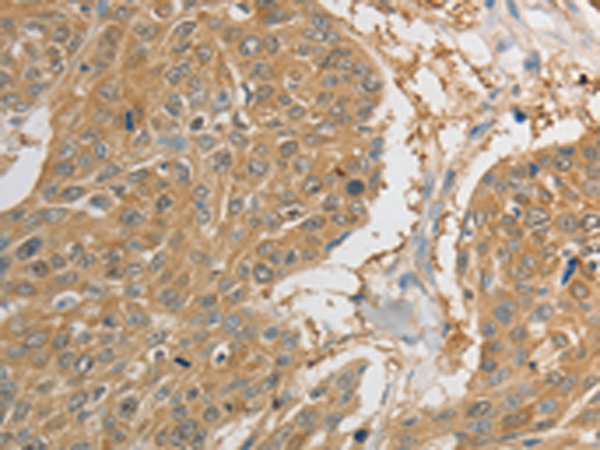

分类: 科研抗体货号: P11103别名: 123F2; RDA32; NORE2A; RASSF1A; REH3P21应用: WB,IHC反应种属: Human, Mouse

分类: 科研抗体货号: P11099别名: PRP; TSA; PRX2; PTX1; TPX1; NKEFB; PRXII; TDPX1; NKEF-B应用: WB,IHC反应种属: Human, Mouse, Rat

分类: 科研抗体货号: P11098别名: PAG, PAGA, PAGB, PRX1, PRXI, MSP23, NKEFA, TDPX2, NKEF-A应用: WB,IHC反应种属: Human, Mouse, Rat